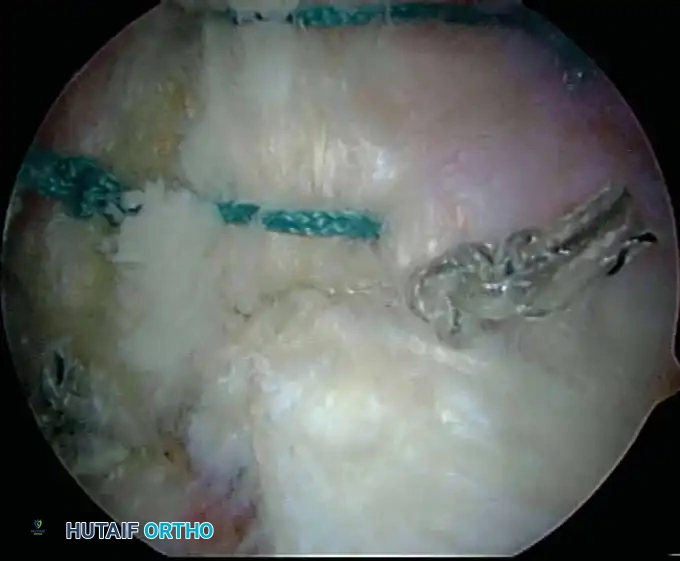

Once diagnostic evaluation is complete and hemostasis is secured, the therapeutic phase commences. Whether performing a SLAP repair, a Bankart stabilization, or a rotator cuff repair, the principles of tissue mobilization, anatomical footprint restoration, and secure biomechanical fixation remain paramount.

Modern arthroscopy relies heavily on suture anchors (biocomposite or all-suture constructs) and advanced arthroscopic knot-tying or knotless techniques. The ability to pass sutures through retracted, fibrotic tissue and secure them under appropriate tension without strangulating the microvascular supply is the hallmark of a master arthroscopist.

* Instability/Labral Repairs: Immobilization in a sling (often with a small abduction pillow) for 4 to 6 weeks. External rotation is strictly limited to protect the anterior capsulolabral repair.